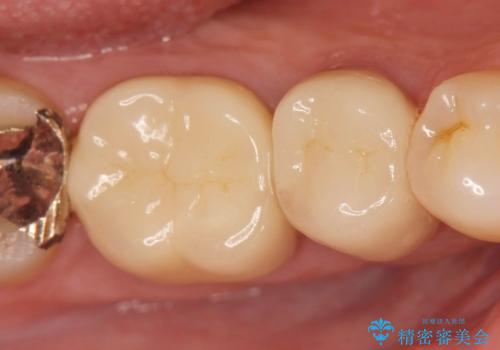

- 26.4万円(ジルコニアクラウン×2・仮歯×2)費用は治療当時の料金となります

治療後、食べ物の挟まりは劇的に改善され、機能性に満足していただけると同時に見た目の審美性にも喜んでいただくことができました。